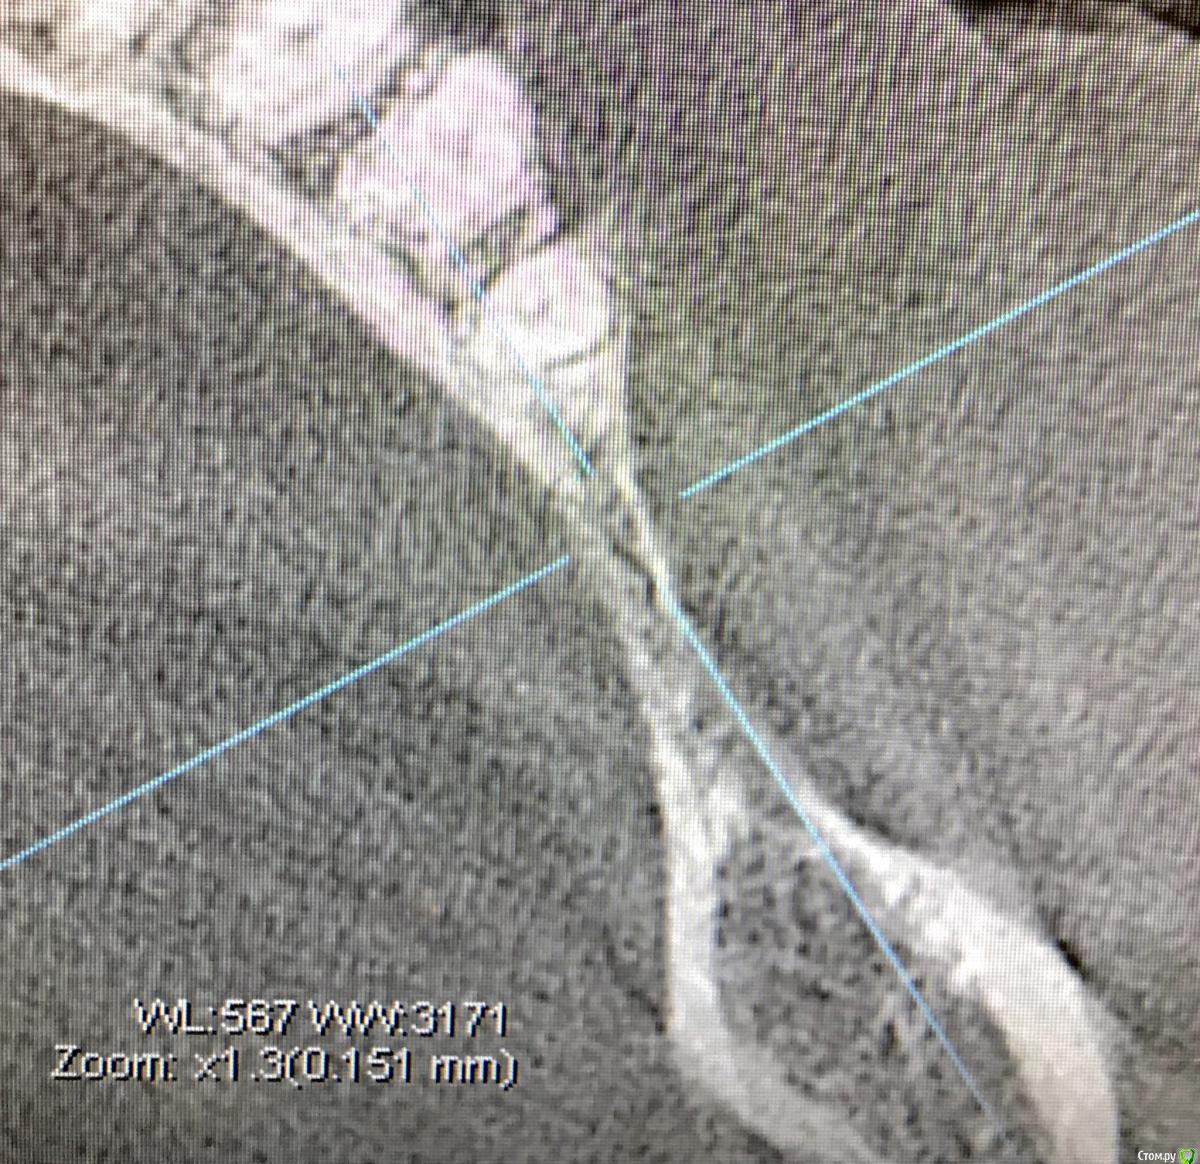

колесников Опубликовано 16 декабря, 2018 Автор Поделиться Опубликовано 16 декабря, 2018 (изменено) Поставлена задача:возместить дефект зубного ряда. Бюджет ограничен. Как видно по кт,для имплантации нет сложностей. Импланты Астра 4.0,поставлены с заглублением в оптимальной позиции. Дефицит прикреплённой слизистой вестибулярно у шеек имплантов возмещён роллом с гребня. Можно было этим ограничится. Однако при протезировании дефицит объема тканей будет очевиден. Роллы фиксированы к подвижной и тонкой слизистой,результат сомнительный,тк нет стабильности. Щечный тяж и скат гребня неминуемо приведут к рецесси слизистой у шеек имплантов. Можно было восстановить объём гребня при помощи нкр,затем лоскут с неба ( 1 год лечения). Или хотябы подсадить сст пожирнее.а потом асл (6мес),на первое время хватило бы. Но . Бюджет ограничен. Сроки тоже. Слово «костная пластика» вызывает панику. Новая задача: минимизировать вмешательства,убрать тяжи,создать объём,небо не трогаем. Проводим тоннельный графтинг. Получаем объём,поднимаем ткани и тяжи не тянут. Роллы получают покой ,стабильность и созревают в кратчайшие сроки. Графт поднадкостнично. Графт стабилен. Графт пропитался кровью,графт созревает. Результат быстрый. Дискомфорта 0. Затраты минимальные. Срок жизни такой пластики ни чем отличается от любой другой,в конечном итоге тает все. Если не стимулировать. Изменено 16 декабря, 2018 пользователем колесников 1 Ссылка на комментарий